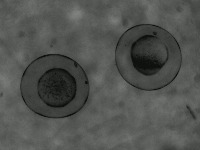

Research & Development: Researchers studying embryo development can use the AliDatabase to automate the process of identifying different stages of zeb1 cells. This can speed up research and reduce the possibility of human error in stage classification.

Medical Diagnosis: In fertility clinics or other medical settings, the AliDatabase can be utilized to identify and sort unfertilized or unhealthy zeb1 cells. This could help in diagnosing certain fertility issues and developing treatment plans.

Educational Tools: The model can be used as an educational tool for biology or medical students. By using AliDatabase, students can better understand the stages of zeb1 cell development and engage with interactive studying methods.

Pharmaceutical Testing: Companies developing drugs or treatments that impact cell growth could use AliDatabase to monitor how zeb1 cells respond at different stages to these drugs, aiding in efficacy and safety tests.

Quality Control in Lab Conditions: The model can be used to identify 'bad' or 'advanced' stages of zeb1 cells, indicating contamination or other issues in lab conditions, thereby assuring the quality of scientific experiments.